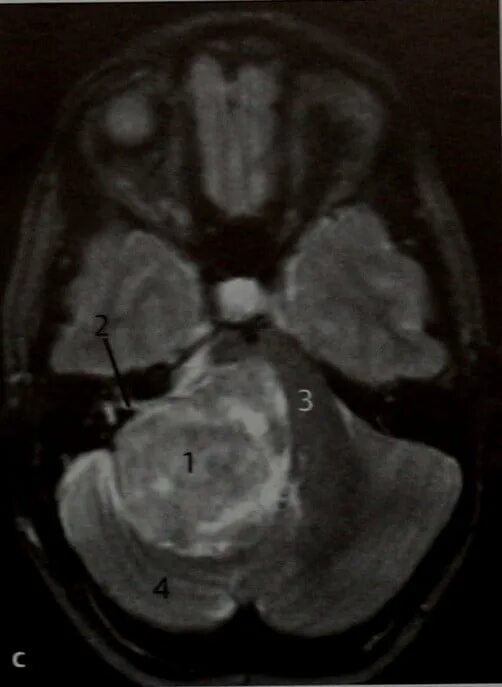

Мрт головного мозга мосто мозжечкового угла